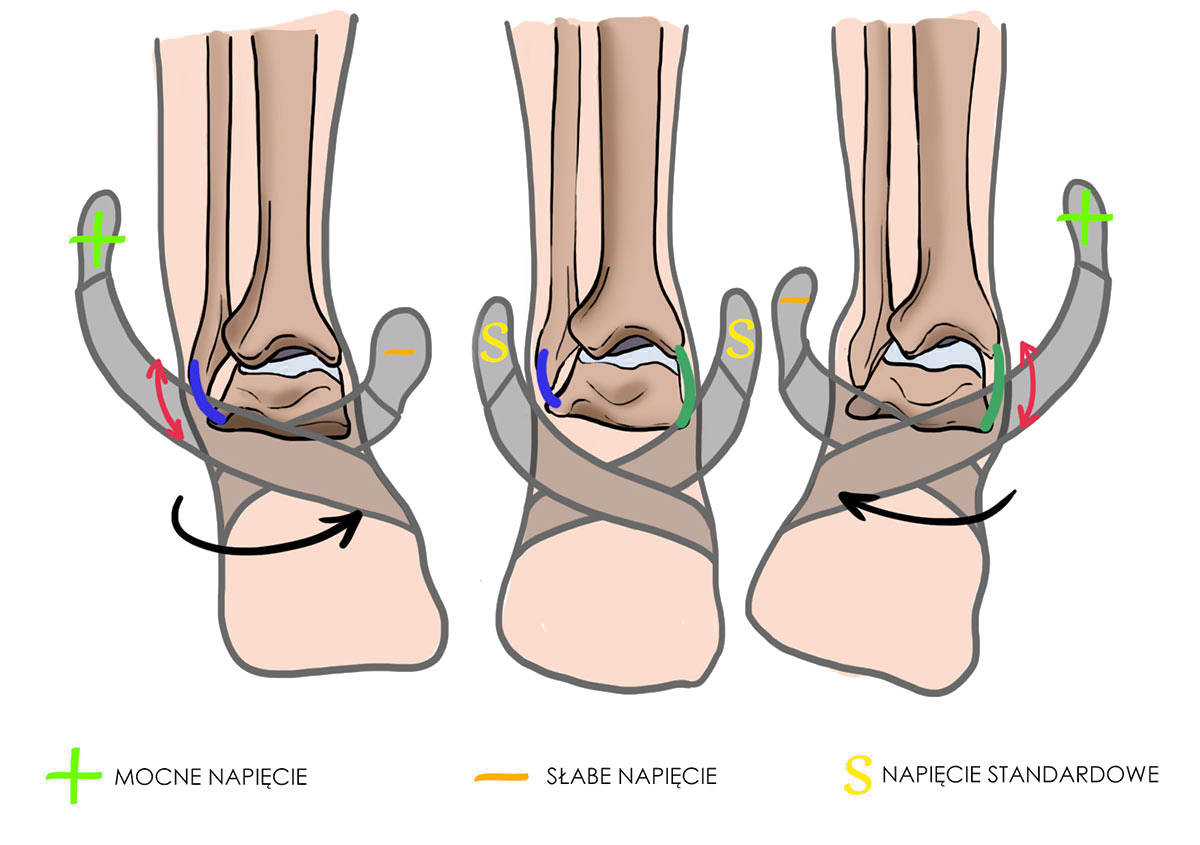

Orteza kostki AM-OSS-05 daje możliwość ustawienia stopy w inwersji lub ewersji.

W zależności od podatności stawu, możemy korygować i ustalać pożądane ustawienie stopy. Taką możliwość osiągamy poprzez regulację siły napięcia jednej z dwóch taśm elastycznych.

W celu korekcji przywiedzenia należy mocniej napiąć taśmę wychodzącą od wewnętrznej strony stopy. Natomiast, w celu korekcji odwiedzenia należy postąpić odwrotnie. Poprzez utrzymanie standardowego napięcia pasów krzyżowych, ustawiamy stopę w pozycji neutralnej.